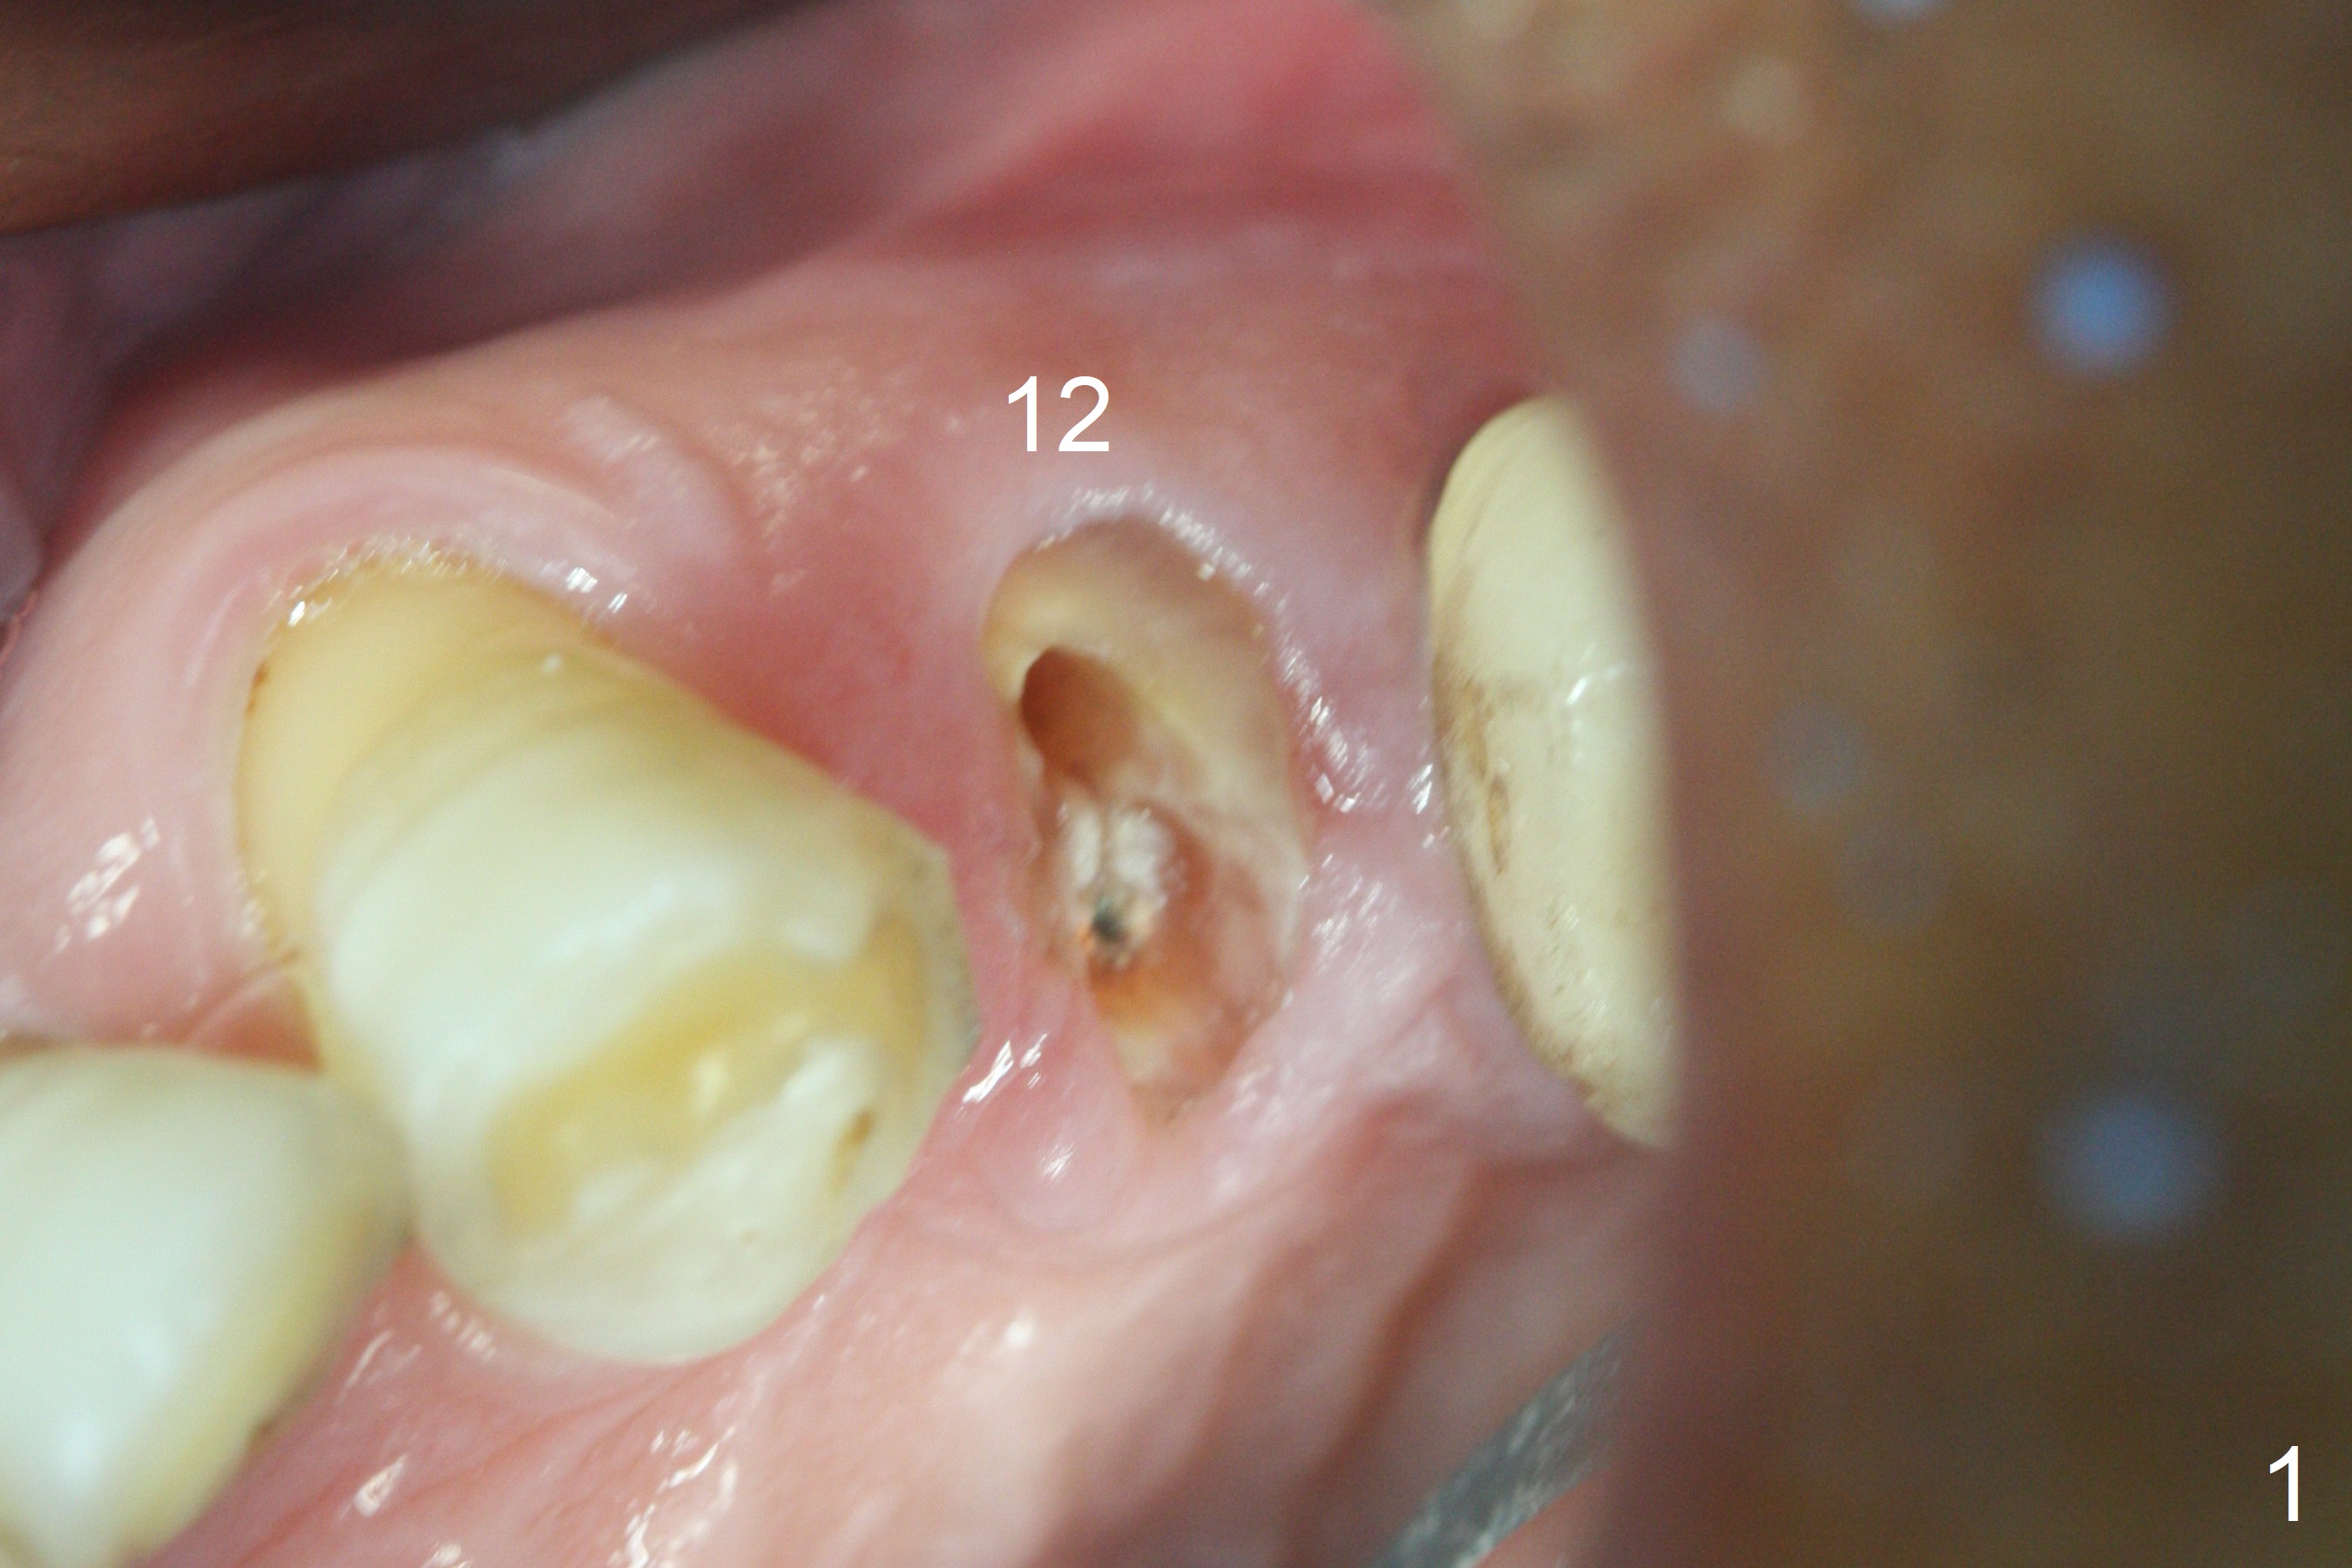

After extraction of the oval-shaped residual roots at #12 (Fig.1), osteotomy is initiated in the palatal socket for 18 mm; since the root of the canine curves distal (Fig.2 red dashed line), the osteotomy cannot afford to move mesial and extend more apical. A 3.8x15 mm implant is placed with > 50 Ncm (Fig.3). With immediate placement of a 4.5x4(3) mm abutment, an immediate provisional is fabricated to close the sockets (Fig.4 P). The provisional has clearance from the RPD clasps (Fig.5). In fact the implant could be longer, as shown by immediately postop panoramic X-ray (Fig.6). The implant seems to be osteointegrated 3 months postop (Fig.7). The tooth #13 is symptomatic with caries (Fig.8 C) 7 months post #12 crown cementation; the #13-15 FPD dislodges. The upper left quadrant is cold and hot sensitive 2.5 months post RCT (Fig.9); although there is mild percussion at #13, pulpal test shows that the tooth #15 has lingering pain. The FPD was recemented temporarily after RCT; it cannot be removed. The implant crown has been loose for several months during the pandemic before he returns 2 years 7 months post cementation. In fact the abutment has been not seated completely (from Fig.3 to 9). The crown/abutment is removed from the mouth; the crown is sectioned and separated from the abutment; the latter is reseated, but incompletely (Fig.10 <). With suspicion of the mesial crestal contact, profile drills 4.6 and 5.5 mm are used without effect. A new (old probably being worn) and longer (easy to turn in the narrow space) abutment is finally seated completely (Fig.11 (no gap)). After occlusal adjustment, abutment level impression is taken for a new crown.